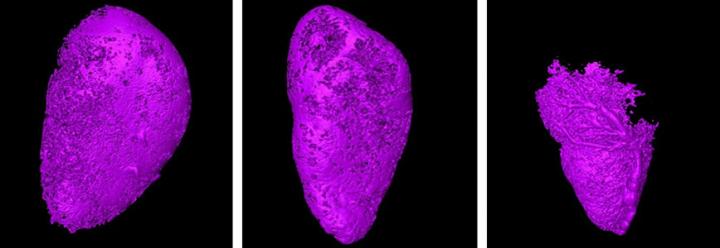

image: Researchers have developed a new method to detect cancer earlier in the lymph nodes involving micro-CT. The micro-CT scans show how a contrast agent is blocked from more and more of the lymph node, indicating tumor development within the first month of infection. view more

Initially, the researchers did not observe any change in the flow of the contrast agent. However, after 28 days of injecting the cancer cells into the lymph nodes, they had divided and grown to a point where they blocked the flow of the contrast agent, creating empty pockets in the scan that did not have any contrast agent.

By comparing the shape of the lymph node and the areas that contained the contrast agent, the researchers were able to get a clear picture of the presence of cancer cells there.